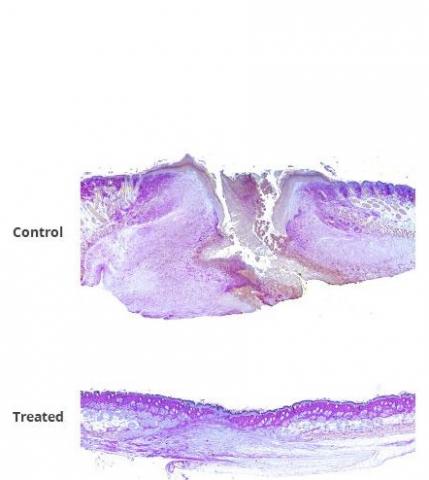

L’auteur principal, le Dr David J. Sharp, professeur de physiologie et de biophysique à Einstein résume ainsi les résultats : « Non seulement la cicatrisation des plaies a été plus rapide et plus complète, mais la régénération de la peau également, avec une bonne restauration des réseaux de collagène et des follicules pileux ». Selon les chercheurs, cette thérapie combinée pourrait réduire le fardeau considérable des plaies chroniques.

La preuve d’efficacité de la combinaison FL2-siRNAs / PluroGel : la combinaison thérapeutique est ici appliquée à des souris modèles d’excisions cutanées ou de brûlures vs témoins (souris traitées avec PluroGel seul et souris traitées avec PluroGel + siRNAs ne ciblant pas FL2). Les plaies ont été traitées le jour de l'excision ou de la brûlure, puis 2, 4 et 6 jours plus tard. L’évaluation finale de la plaie a été effectuée 14 jours après la blessure. L’expérience montre que :

- 4 jours après le traitement des plaies par excision, les plaies des souris des deux groupes témoins étaient presque 2 fois plus grandes que celles des souris traitées avec l'association FL2-siRNAs / PluroGel ;

- plusieurs souris traitées par la thérapie combinée avaient également des follicules pileux sur le site de la plaie, alors qu'aucun n'a été observé chez les souris témoins ;

- chez les souris traitées pour brûlures, à 14 jours, les plaies des souris des 2 groupes témoins sont plus larges d'un tiers que celles des souris traitées avec l'association FL2-siRNAs / PluroGel ;

- les plaies de brûlure de toutes les souris traitées avec la combinaison FL2-siRNAs / PluroGel sont complètement refermées au jour 14 vs 25% à 30% des plaies des souris des groupes de contrôle.

La combinaison FL2-siRNAs plus PluroGel apparaît ainsi prometteuse : en réduisant les niveaux de FL2 dans les cellules de la peau, le FL2-siARNs aide les cellules à recouvrir et combler le site de la plaie beaucoup plus rapidement qu'elles ne le feraient normalement. Un mécanisme essentiel pour minimiser les cicatrices et éviter que la plaie ne devienne chronique. Enfin, en hydratant la plaie et en inhibant les microbes, PluroGel offre un atout supplémentaire à la cicatrisation.